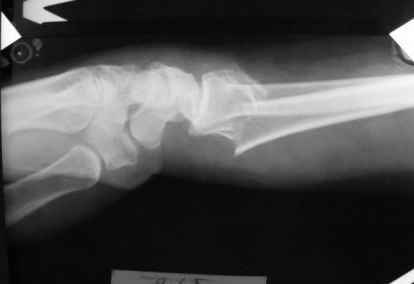

Уважаемые коллеги.Прошу обсудить случай лечения перелома дистального метаэпифиза лучевой кости. Ситуация скандальная и крайне неблагоприятная. Больная с патологической обстоятельностью мышления, склонностью к сутяжничеству, патологическими умозаключениями, не поддающимися коррекции (см. психиатрию, правда офиц. диагноза нет). В данном случае есть ряд ошибок с нашей стороны, прежде всего в отношении качества ведения документации (за что получил административное взыскание, по делом мне дураку). В остальном- придерживались в лечении подхода классический советской школы. Так как умную операцию…… сами знаете… 15.12- перелом луча в Москве. Там же репозиция, гипс. Дальнейшее лечение у нас в ЦРБ. 20.12.- вторичное смещение в гипсе21.12- под внутривенным наркозом- репозиция, гипсовая лонгета. Дальше начинается самое интересное. После репозиции больная заявила, что я (репозицию делал я) порвал ей все связки в суставе, посинел у нее 5 палец, якобы я за него тянул и т. д. На самом деле на 2 сутки после репозиции рука немного отекла и было незначительное сдавление гипсом, который был ослаблен. Дальнейшее лечение консервативное. Через 6 недель- гипс снят, назначено ЛФК. Пациентка крайне недовольна. Говорит, что на снимке у нее выступает кость, я ей сломал руку и.т.д. В общем началось. Пациентка прочитала в интернете наверное все, что есть по данной травме.По заключениями рентгенологов и консультанта из КДЦ областной больницы - стояние отломков допустимое. Объективно говоря- снижена высота лучевой кости, диастаз лучелоктевого сочленения, и не сросся шиловидный отросток. однако на РКТ при сравнении с другой стороной- разница незначительная. Дальше в одной из больниц нашей области и одной из больниц Москвы (вроде бы КГБ 53) врачи сказали, что репозиция сделана плохо. Нужна операция (восстановить длину лучевой кости), даже один из них предложил РЕДРЕССАЦИЮ (хи-хи) с наложением аппарата Илизарова. Что это для данной больной- радость неописанная. (см. описание психического статуса). Ничем другим, кроме зарабатывания дешевого авторитета объяснить данный факт не могу.Кстати, у больной еще нейропатия локтевого нерва.Для разрешения конфликта больная направлена на консультацию в ЦИТО на 03.03.11.

Заключение: Консолидированный в неправильном положении перелом дистального метафиза левой лучевой кости. Ротационная контрактура левого предплечья. Рекомендовано- разработка, консультация через 2 месяца.

Объективно: пронация почти полная, супинация ограничена, ладонная флексия около 20, тыльная 10. Гипостезия в зоне инервации локтевого нерва. Незначительный отек. Хват кисти полный. Сила 4 балла.

В общем, типичная картина раннего восстановительного периода после снятия гипса. Визуально конечность не изменена.